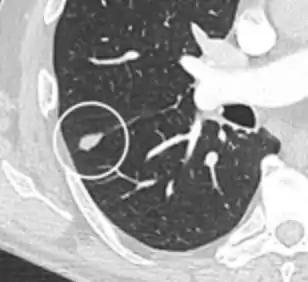

Part solid nodule.[9]

Ground glass opacity nodule.[9]

Nodule with pleural retraction.[9]

In this case, pleural retraction is seen as a triangular fat component.[9]